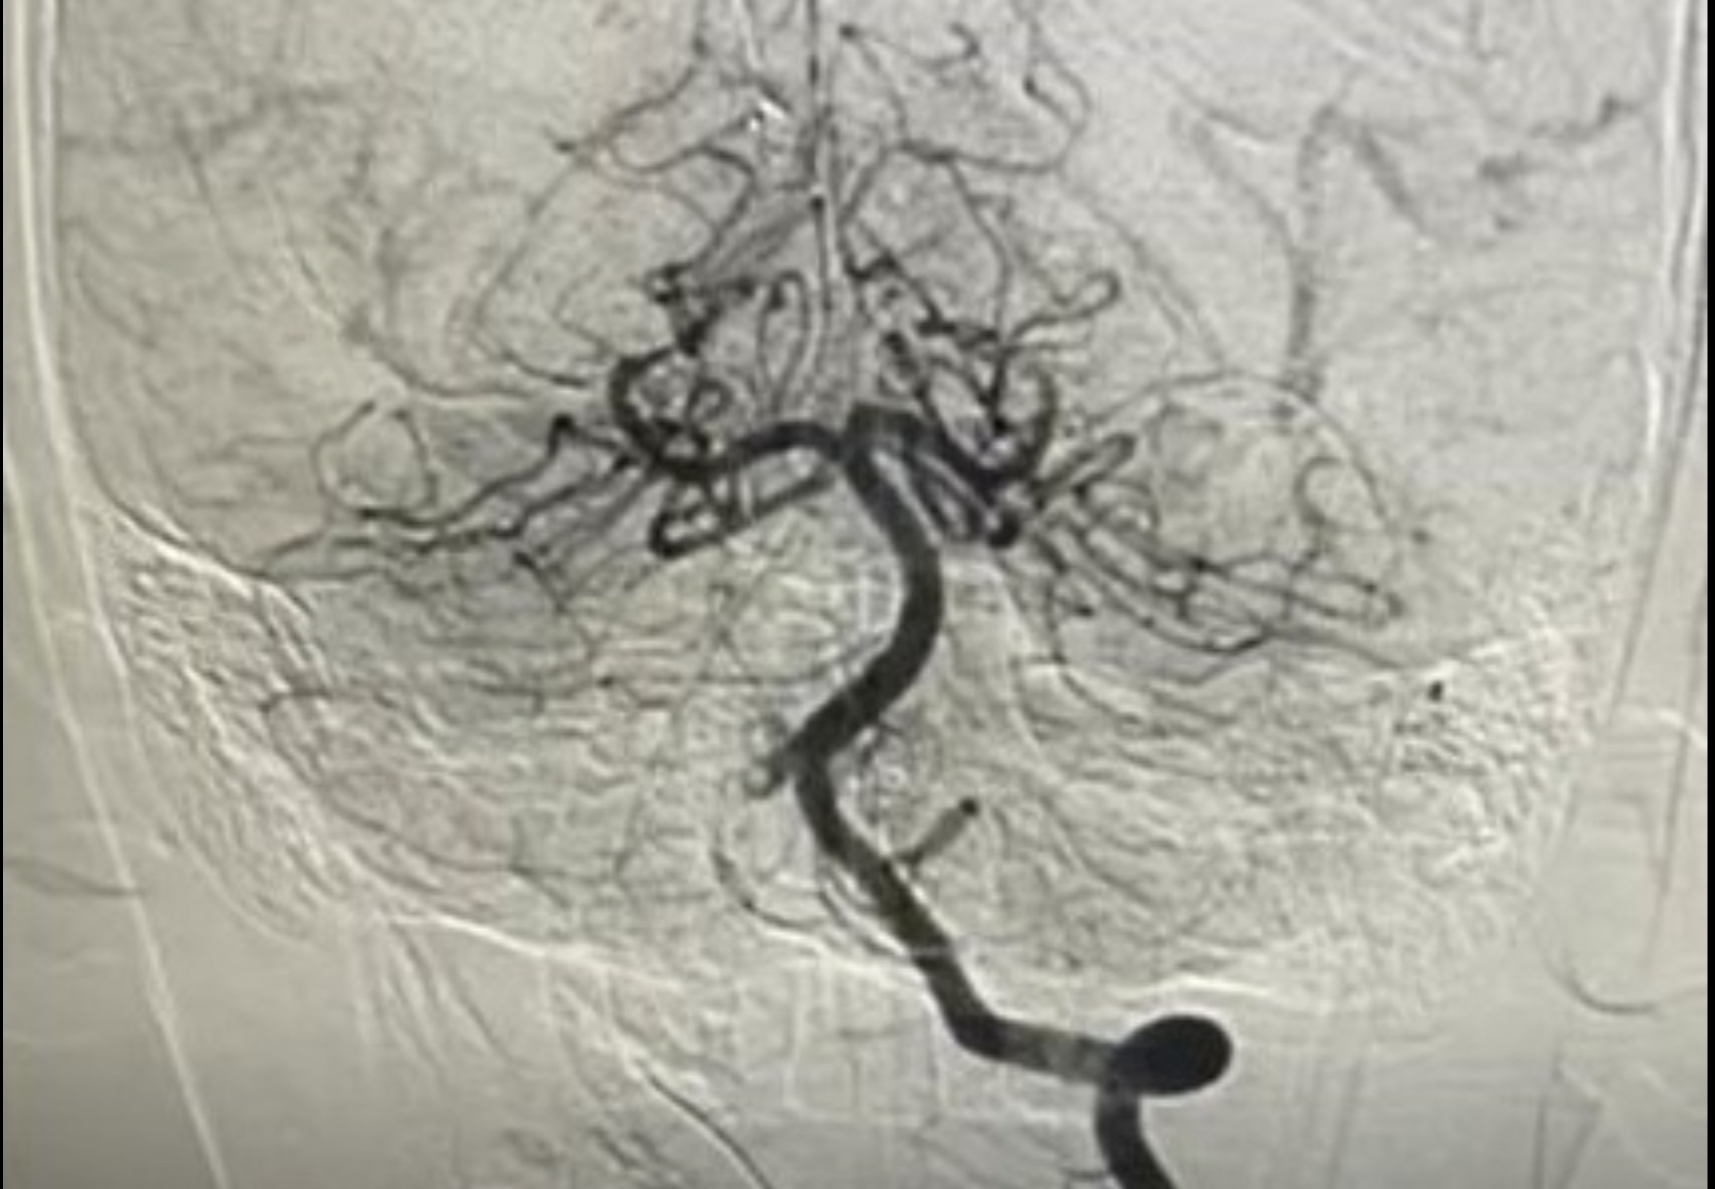

Ảnh chụp mạch máu xóa nền DSA của bệnh nhi 10 tuổi bị nhồi máu não cấp – Ảnh: Bệnh viện cung cấp

Bệnh viện Nhi đồng thành phố (TP.HCM) vừa điều trị thành công một bé trai 10 tuổi bị nhồi máu não cấp hiếm gặp, giúp tránh nguy cơ liệt nửa người vĩnh viễn nhờ can thiệp nội mạch kịp thời. Trước đó bé không bị chấn thương, chỉ tham gia hoạt động thể thao.